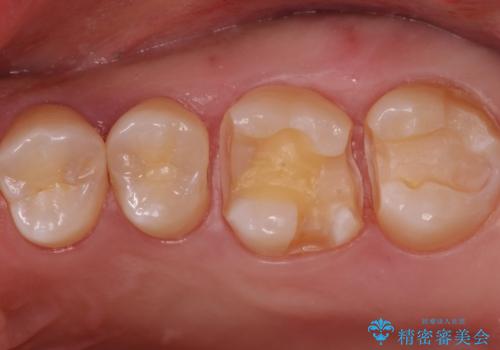

歯と歯の間の虫歯 インレーでの治療(セラミック・ゴールド)

- 銀歯のやり替えと虫歯の治療をご希望で来院された患者様です。

一番奥の歯は外から見えにくい部分であるためゴールドインレーで修復します。

その他はセラミックインレーで修復します。

- 左上46:セラミックインレー/77,000円×2 左上7:ゴールドインレー/77,000円×1費用は治療当時の料金となります